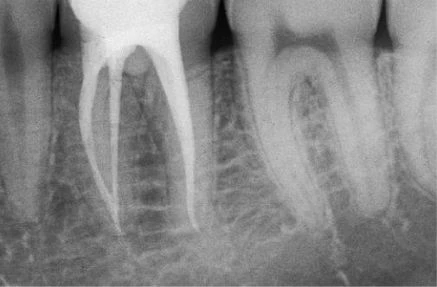

Ống xa thường có hướng khá thẳng, ngoại trừ hầu hết phần chóp thì thường nghiêng xa (hình 11.117). Lý do vì sao cong về phía xa cũng dễ hiểu, nếu như biết rằng hàm dưới vẫn còn phát triển về phía gần khi răng đã hoàn thành việc đóng chóp. Chóp chân răng hình thành xung quanh một cuống mạch máu, vào một thời điểm nào đó cũng sẽ nghiêng theo chiều gần xa.

Điều quan trọng là phải biết ống tủy có cong và dùng dụng cụ nhỏ, uốn cong trước. Một dụng cụ thẳng với kích thước không phù hợp sẽ bị cản trở bởi thành ngoài của chỗ cong, tạo cảm giác như dụng cụ đã đến tiếp xúc với chỗ thắt ở phía chóp hoặc chỗ nối cement ngà. Một dụng cụ nhỏ, uốn cong trước thì lại có thể dễ dàng vượt qua được đoạn cong ở phía chóp.

Hình 11.117. A. Phim trươc điều trị: ống tủy được điều trị bởi bột nhão iodoformic  B. Làm cong file 8: dễ dàng qua chỗ cong của ống tủy  C. Phim sau điều trị. D. Phim 2 năm sau. Chỗ cuối của vị trí trám bít ống tủy cách đỉnh chóp ít nhất 3mm.